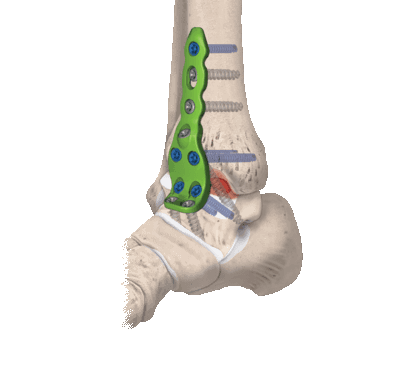

Артродез голеностопного сустава: виды замыкания, показания, осложнения

Артродез голеностопного сустава - оперативное вмешательство по искусственному сращению сочленяющихся суставных поверхностей голеностопа в физиологически выгодном для функционирования ноги положении. Основной целью хирургического лечения является придание опоропрочности проблемной зоне посредством полного блокирования ее подвижности (создания анкилоза). Обездвиживание достигается за счет жесткого соединения примыкающих концов костей сустава между собой специальными фиксаторами из металла (спицами, винтами, штифтами и пр.). Это позволяет прочно срастись суставным поверхностям друг с другом под нужным углом, то есть, привести сочленение в полное неподвижное состояние, что поможет пациенту избавиться от сильной боли и нестабильности стопы.

- Внутрисуставный. В процессе хирургии выполняется вскрытие капсулы сустава с последующим удалением поврежденного гиалинового хряща с поверхностей костных элементов. После репозиции костей в выгодном положении выполняется их фиксация металлическими приспособлениями.

- Комбинированный. Эта техника подразумевает сочетание в одном хирургическом процессе двух способов: внутрисуставного и внесуставного. Так, хрящевые структуры с сустава полностью счищаются, внедряется аутотрансплантат, который фиксируют специальными металлическими пластинами.

- На нижнюю треть бедра накладывается пневматический жгут. Далее создают доступ, совершая скальпелем линейный кожный разрез вдоль сустава. Разрез равен примерно 10 см.

- На следующем этапе выполняется вскрытие и надежная супинация сустава, которая облегчит работу с очередными манипуляциями.

- Затем подготавливаются поверхности большеберцовой и таранной костей. Подготовка включает резекцию хрящевых тканей хирургическим долотом, удаление окостенения.

- Дальше стопа выводится из порочного положения. Большеберцовый элемент и таранный компонент плотно сопоставляют друг с другом в удобной с точки зрения физиологии позиции. Достигнутая позиция скрепляется металлической конструкцией необходимого типа.

- Используемые операционные ходы на завершающем этапе закрывают при помощи послойного ушивания мягких тканей с оставлением дренажа.